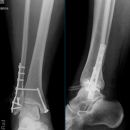

Sprunggelenk